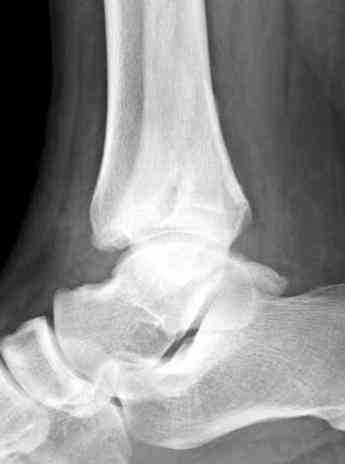

Здесь представлено решение похожей проблемы. Больной в течение года лечился консервативными мерами, и боли в голеностопе были основным показанием к операции.

Проведена обычная стандартная процедура по исправлению неудовлетворительного состояния голеностопного сустава, где кроме удлинения малоберцовой с применением compression tension device за проксимальный конец пластины, проведено замещение трикортикальным графтом из крыла, освобождение синдесмоза и медиальной щели от

фибротических масс с фиксацией.

"артродез против восстановления", но можешь поверить мне, что несмотря на продолжительный период до восстановления сустава, после таких операции больные чувствует намного легче чем после расхваливаемого артродеза.